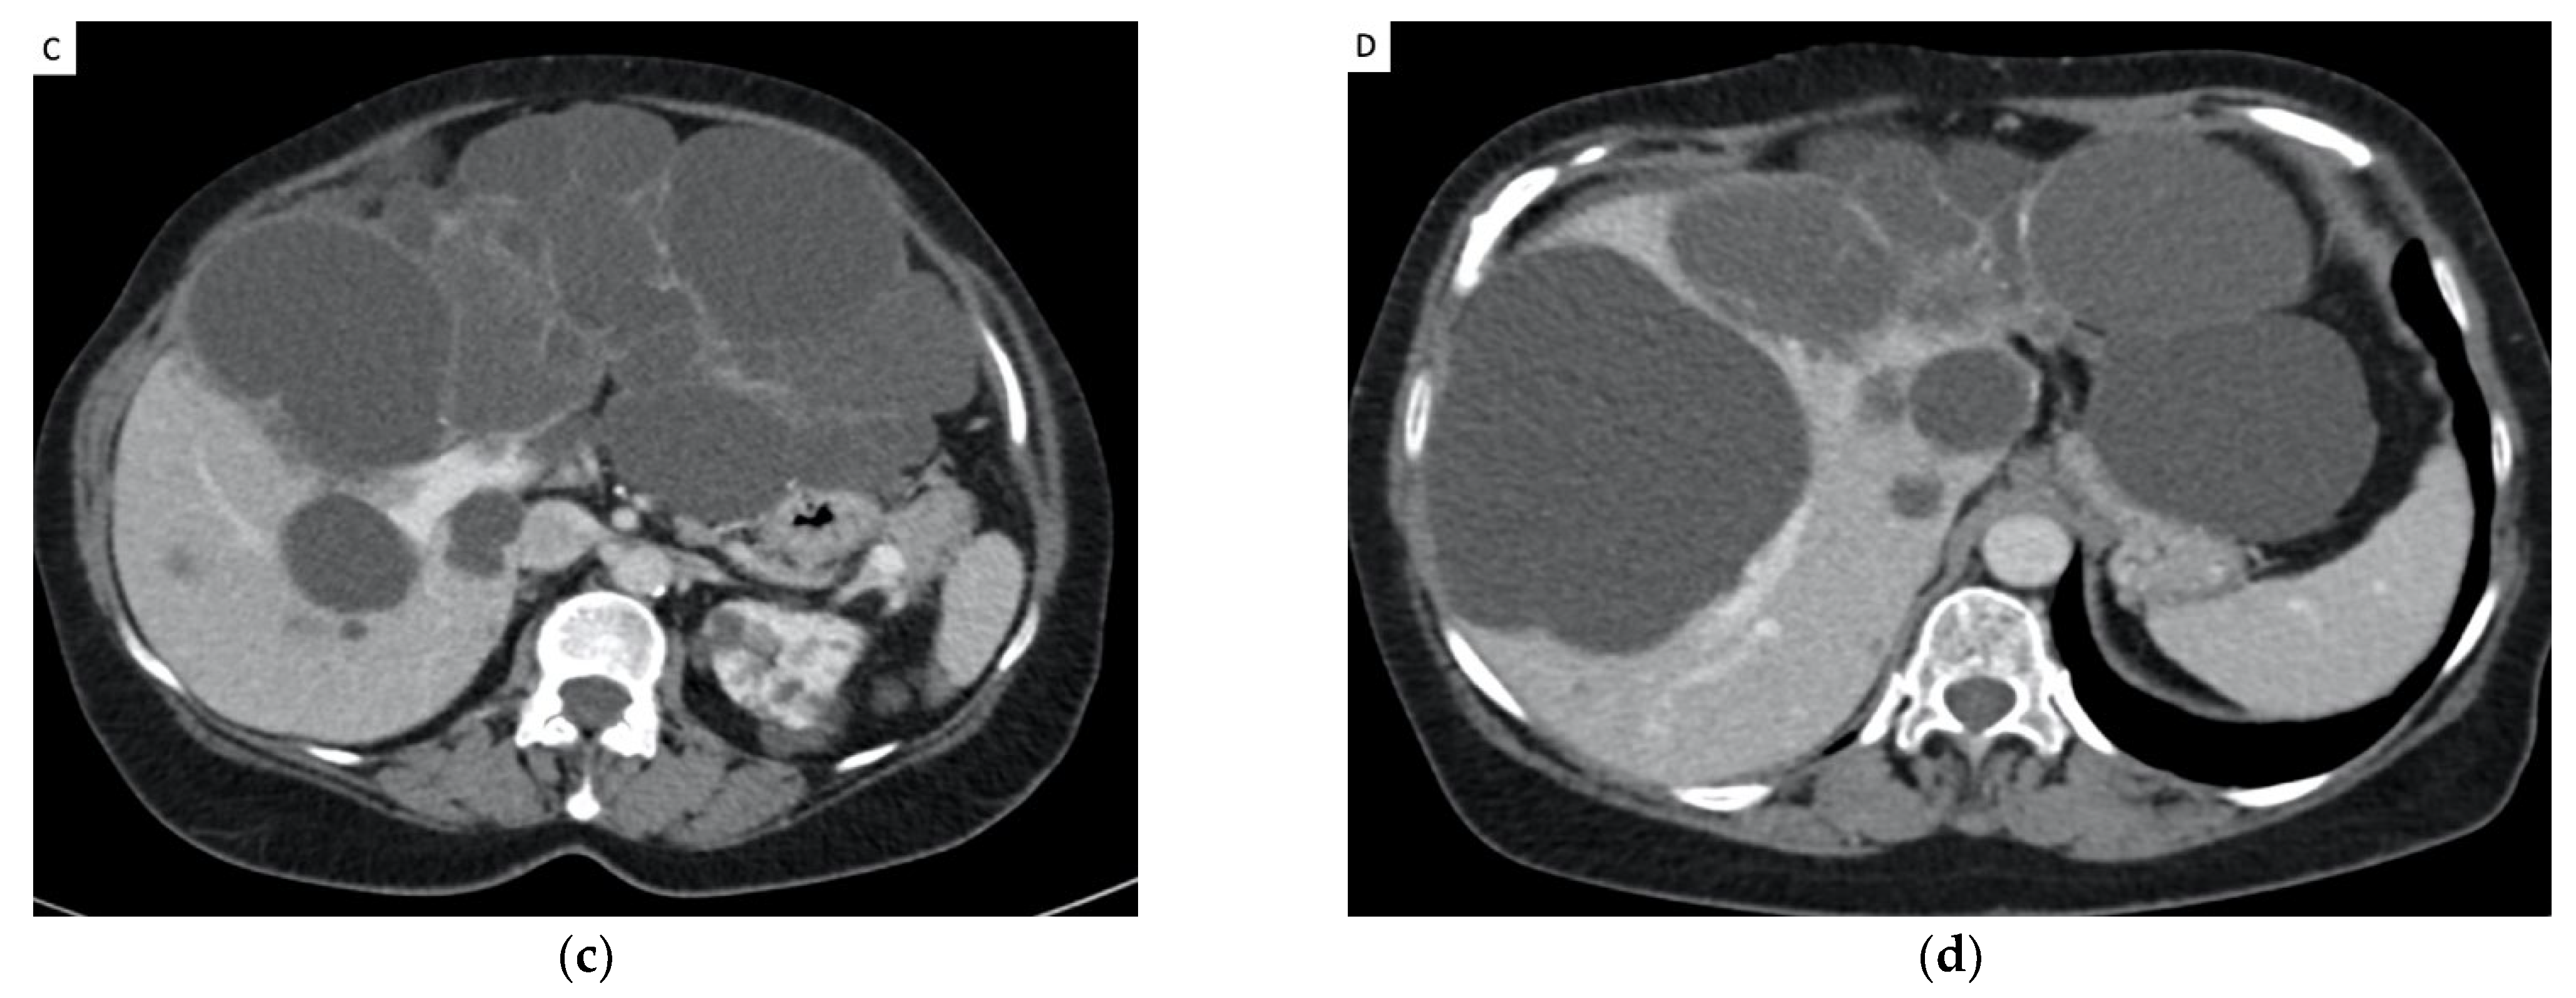

3.4. Reduction in Hepatic Volume (Figure 2 and Table 3)